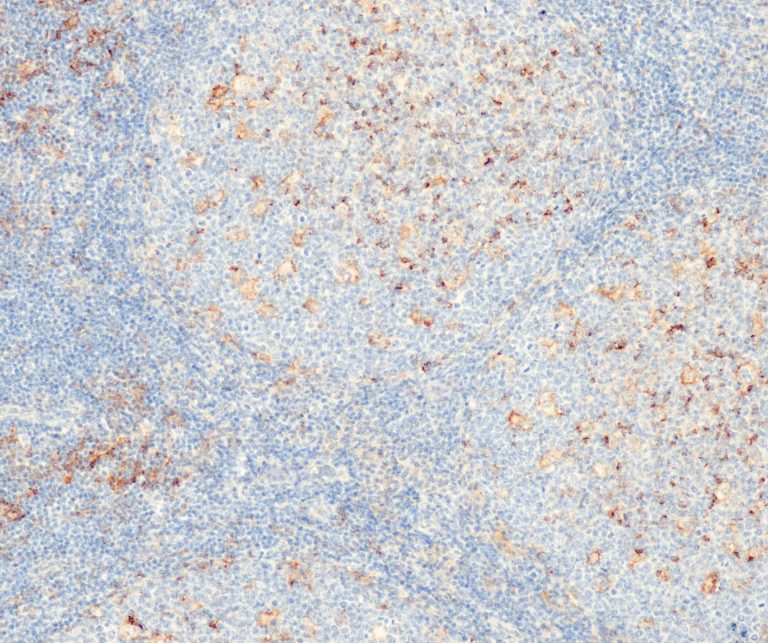

Hematopathology